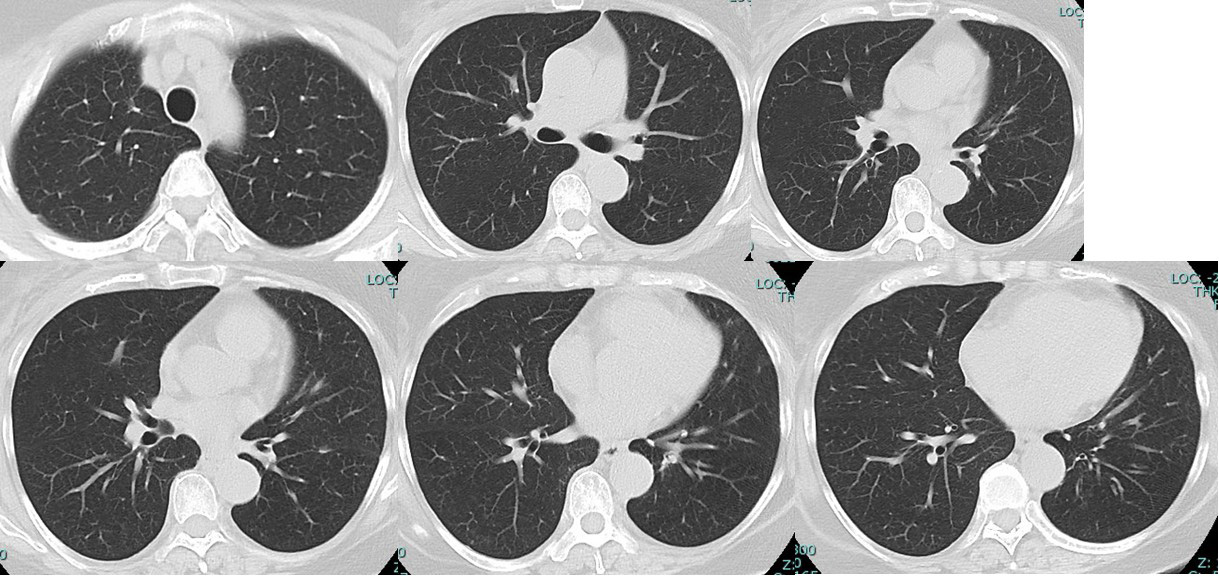

case 1 QA管理番号12566さん 診断時、「多発転移」

手術適応無、luminay typeであり薬物療法の第1選択としてCDK4/6 inhibitor+hormone開始

この前医での「分子標的薬+ホルモン療法」による治療効果 2022/8/2~2025/2/5 (2年半)

この(分子標的薬+ホルモン療法だけの)2年半の効果

肺 かなり効いている

肺転移は(分子標的薬だけで)コントロールされている。

①「多発肺転移」は画像上かなり小さくなっているのに「胸の腫瘍は小さくならない」

転院、そして手術 Bt+Ax+Ic, (レベルⅢまで郭清しましたが、幸いリンパ節転移はレベルⅠに1個のみでした。乳腺腫瘍は33mm)

術後は根治を目指しanthracycline+taxaneを施行。

anthracyclin終了時の時点でのCTでcCR

きっと、12566さんが望んでいたのはこれなんだよ。

病変が(少なくとも)画像上消失した状態。